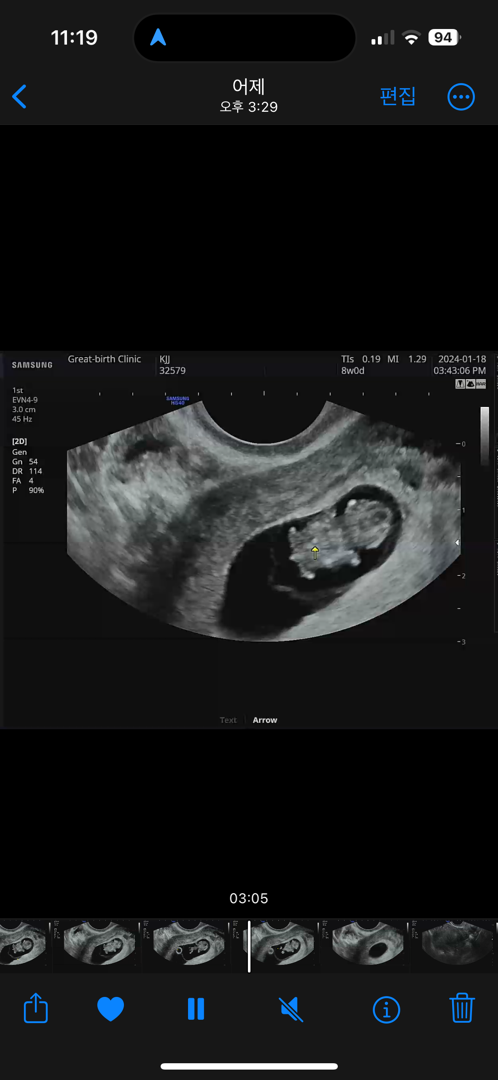

8주차젤리곰

8주차 젤리곰 확인하고왔는데요, 가운데 저게 생식기일까요 탯줄연결일까요 ㅜㅜ 8주차에도 생식기 구분이가능한가요

아뇨꼬리에요! ㅎㅎ 정확히는 사람마다 다르겠지만 14주쯤 지나면 들어가거나 남아있거나 생식기가 보일거예요! ㅋㅋㅋㅋ 8주면 여전히 꼬리입니다 ^_^

저도 8주에 꼬리 같은 거 보여서 생식기냐고 여쭤봤는데 생식기는 아직 형성 전이라고 하더라고요 ㅋㅋㅋ 꼬리 퇴화 과정 같애요

꼬리일꺼예요 점점 성장해가면서 여자아이면 들어갈거고 남아이면 표시가 드로나겠죠??